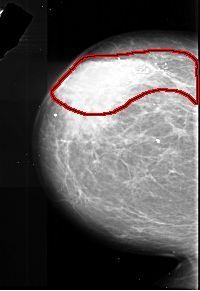

FILE: A_1017_1.LEFT_CC.OVERLAY

TOTAL_ABNORMALITIES 1

ABNORMALITY 1

LESION_TYPE CALCIFICATION TYPE PLEOMORPHIC DISTRIBUTION SEGMENTAL

ASSESSMENT 5

SUBTLETY 5

PATHOLOGY MALIGNANT

TOTAL_OUTLINES 1

BOUNDARY

LEFT_MLO LINES 5866 PIXELS_PER_LINE 3466 BITS_PER_PIXEL 16 RESOLUTION 42 OVERLAY